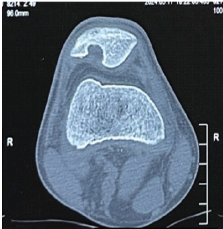

Aneurysmal Bone Cyst Presenting as a Pathological Subtrochanteric Femur Fracture in an Adolescent: A Case Report

Chandrashekhar R Rai , Sandeep V Gavhale , Vijaysing Chandele , Alok P Yadav , Chinmay S Torne , Vishal B Karpe

………………………………p.89-93